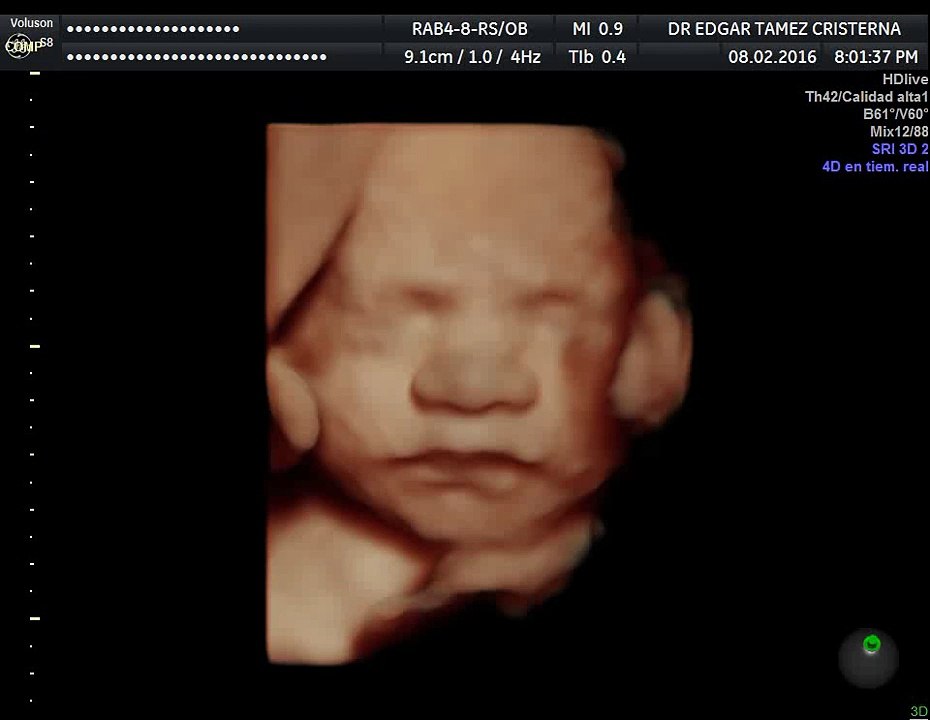

Ultrasonido 4D HD Live Embarazo de 29 semanas 0:21

Ultrasonido 4D HD Live Embarazo de 29 semanas

Fredrick Luna 1 views